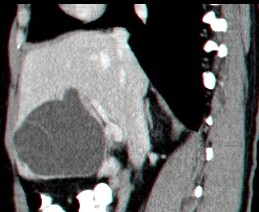

- בטומוגרפיה ממוחשבת של הבטן ניתן לראות גוש בכבד עם פלס אוויר בתוכו ונוזל בעל סמיכות גבוהה (תצלום 40.10). ממצאים אלה הופכים את האבחנה לוודאית.